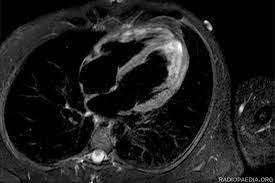

where, $\beta$ is represented as the extraction of the characteristics, and F is denoted as the detected textural features in the acquired inputs. Now the representation of the dimension’s operation is performed. This is the process of denoting the data in both the 2×2 to 16×16 dimensions. This plays an important role in cardiac MRI analysis. This operation engages the structuring of the extracted features and textural information in two distinct dimensions, producing the complete representation of the cardiac data. Therefore, in the 2×2 dimensions, the refined details and localized variations within the acquired input MRI input images are captured. This permits for the more explored assessment of the particular regions of the heart, making it fit for the detection of the irregularities within it. The dimension representation process is illustrated in Figure 2.

The input $\gamma$ is used for extracting $\mathrm{F} \forall \beta$ such that $\mathrm{F} \leq \beta$ condition is to be satisfied. Based on the $\gamma(\mathrm{N})=\frac{\mathrm{N}}{2} \forall \mathrm{n} \in \mathrm{N}$, the $\alpha$ is performed in representing the $\gamma$ at its least and maximum formats. In this representation, the $F$ is validated based on available $\gamma^{\mathrm{n}-1} \forall \mathrm{~N}$ such that $\widehat{\beta}=N \odot \beta$ is the idle condition. Therefore, for the $\mathrm{F} \leq \beta$ satisfying condition, segmentation is pursued (Figure 2). Also, the $16 \times 16$ dimension provides an expanded perspective by integrating the data over larger cardiac image areas. This dimension is important for dehiscing the frameworks and overall cardiac structure and functionalities. By denoting the data in both dimensions, the algorithms assess the comprehensive dataset that associates the refined data with the precision and reliability of cardiac disease detection and diagnosis. This dimension representation improves the utilization of the MRI data in enhancing patient care and its outputs. The process of the dimension representation of the acquired data is explained in the equation below:

Figure 2. Dimension illustration